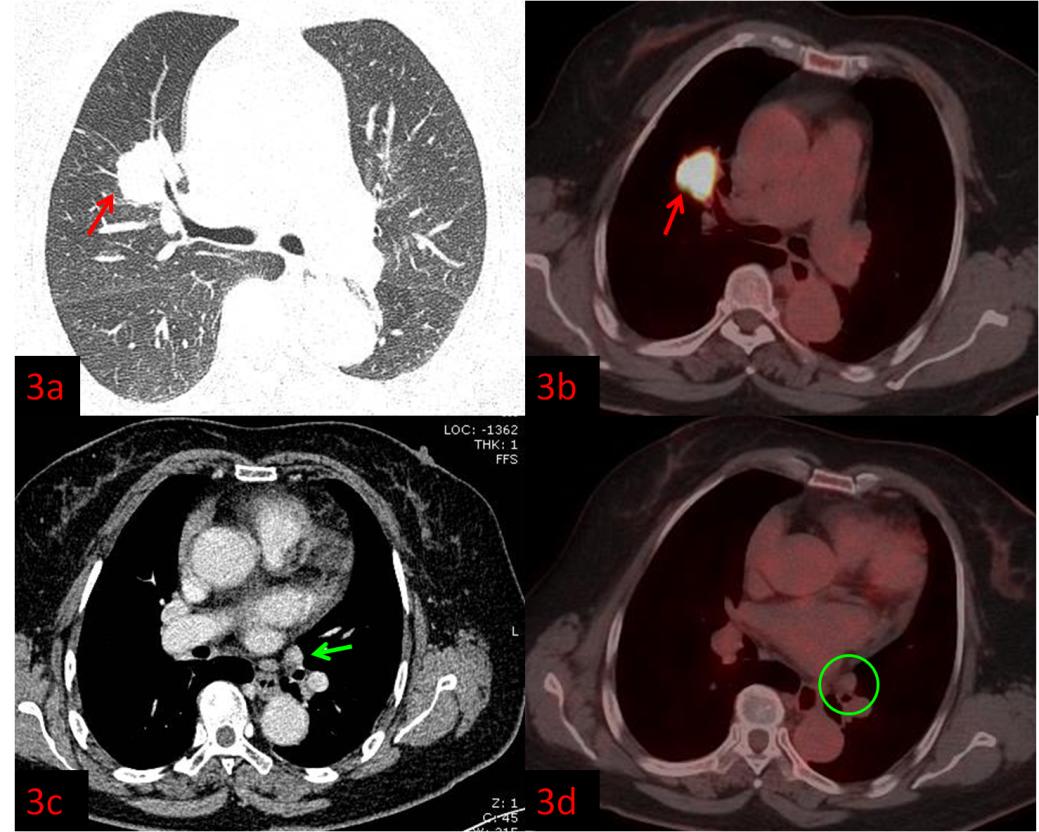

例3:老年女性,右肺上葉病變(紅箭)。強(qiáng)化CT示左肺門腫大淋巴結(jié),轉(zhuǎn)移不能除外(圖3c綠箭),初步分期為ⅢB,無法行手術(shù)根治。而PET/CT顯示淋巴結(jié)FDG代謝不高,考慮良性(圖3d綠圈),患者分期降為ⅡB,于是進(jìn)行了根治性手術(shù)。術(shù)后病理:右肺腺癌。